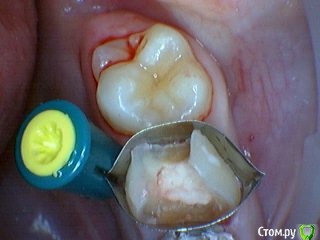

Давлетшин Опубликовано 29 декабря, 2017 Поделиться Опубликовано 29 декабря, 2017 (изменено) Друзья. Расскажите, не поменялось ли ваше отношение к пульпотеку и пр.Почему пломбы поверх пульпотеку такие ужасно жёлтые? Что сделать можно. Или что я делаю не так? "Друзья" так приятно перед новым годом. К пульпотеку не поменялось (устраивает вполне) , к пульподенту скептическое отношение, хоть и тоже работаю. Пломбы сразу желтые или через полгода - год- два? Очень тяжело что то советовать он лайн не видя как человек работает. В фото первая цифра пациент, вторая-третья номер зуба, четвертая порядок фото. Я после наложения пульпотека , стараюсь убрать излишки, или аккуратно на устья каналов накладываю, в пульповую камеру СИЦ, и сверху пломбу, Убрать излишки и со стенок, аккуратно в том числе и бором. В третьем клиническом случае, неудача. Зуб удалил сам же через 3 месяца. причину вижу в том что на рентгене не увидел (или так сделали снимок?) вертикальный тип рассасывания практически до бифуркации., может и потому что ребенок ОЧЕНЬ плохо сидел. За фото не пинайте сильно, не инстаграмм все таки,да и тяжело ребенка лечить и фотки делать. или наоборот пинайте может лучше начнем фоткать. P.s. Добавлю протокол как лечу с пульпотеком, хр.фибр.пульпит1. анестезия2. кофер ( если дает)3. раскрытие кариозной и пульповой камеры4. удаление коронковой пульпы маленьким эскаватором, я стараюсь "отрубать" пульпу5. остановка кровотечения сухим ватным шариком, 0,5-1-2 минуты6. пульпотек на устья7 СИЦ в пульповую камеру8 со стенок остатки пульпотека соскребаю бором фиссурным , цилиндрическим, там же фальц9. Пломба. может что то и зыбыл ну и оценка только позитивная перед НГ Изменено 29 декабря, 2017 пользователем Давлетшин 2 Ссылка на комментарий